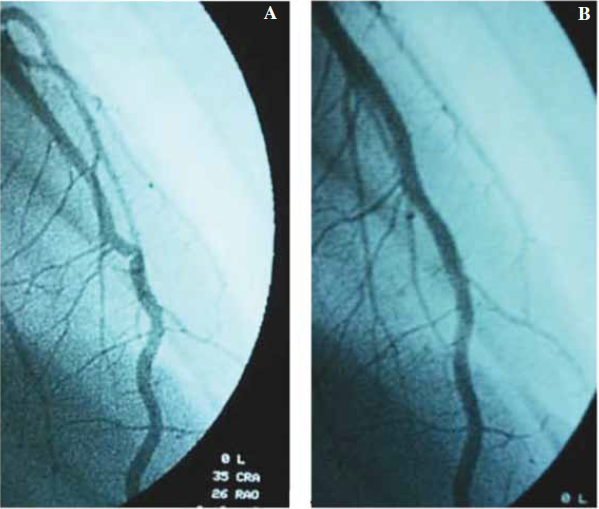

Paciente masculino de 17 años sin factores de riesgo cardiovascular ni antecedentes familiares de relevancia, presentó paro cardiorrespiratorio mientras se encontraba realizando actividad física (jugando al futbol), se comienza con reanimación cardiopulmonar en el lugar, trasladándose a una institución médica, donde se constató un ritmo de fibrilación ventricular requiriendo cardioversión eléctrica que restauró el ritmo sinusal, quedando en asistencia mecánica respiratoria. El electrocardiograma post cardioversión (Figura1) evidenció una injuria subepicárdica en cara anterolateral, realizándose cinecoronariografía, donde no se observaron lesiones ateromatosas en arterias epicárdicas, y como hallazgo se evidenció la existencia de un puente muscular en tercio medio de arteria descendente anterior con colapso sistólico (Figura 2). El ultrasonido intracoronario y la medición de la reserva fraccional de flujo no evidenciaron disminución del flujo coronario en la región de puente miocárdico.